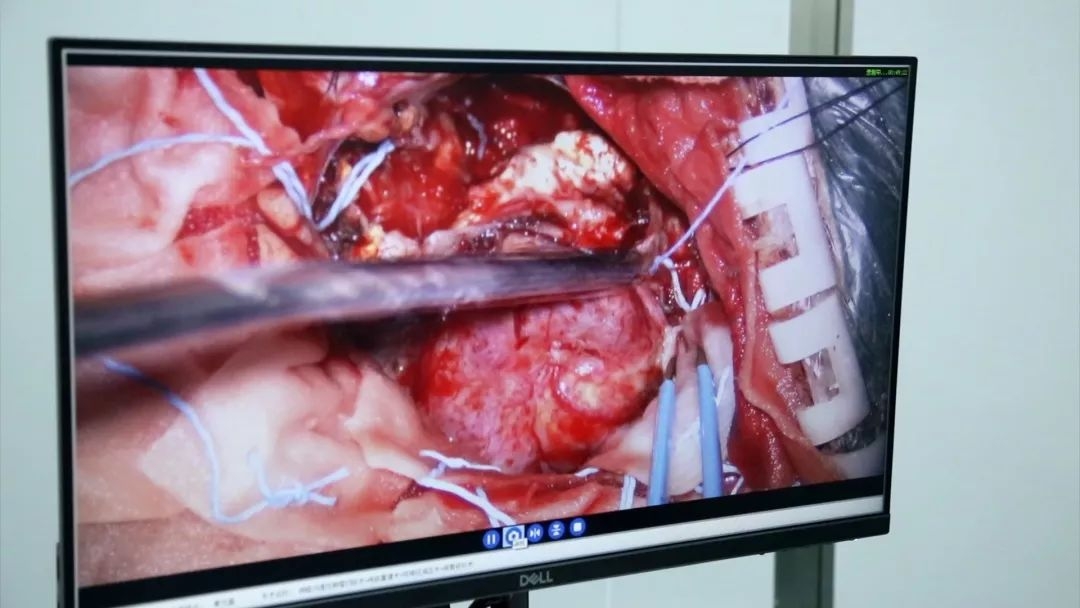

显微镜手术中

高清文件的存档

该显微镜还配有手术全程数码记录系统,可录下手术全过程,为临床科研提供生动、翔实的资料。录像系统放置到显微镜的支架上,视频监视器被灵活的连接在显微镜支架上,使手术可以清晰显示在高清显示器上。

显微镜显示器